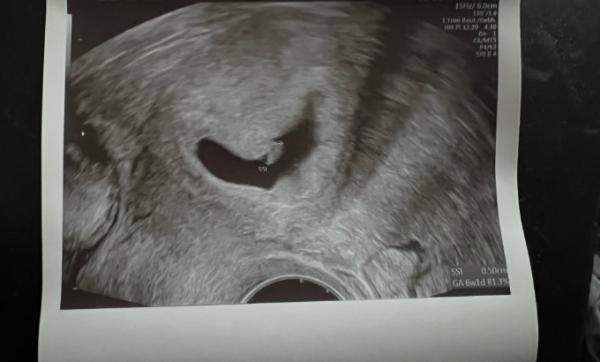

Ich kann es immernoch nicht glauben. Es wächst ein kleines Leben in mir. Letzte Woche der positive Test und heute konnte ich schon den Herzschlag hören. Ich hätte nie gedacht was das für Emotionen in einem Auslösen kann. Mir kamen direkt die Tränen. Ich bin sehr glücklich und freue mich so sehr auf das kleine Wunder < 3

Bild zu Erster Termin beim FA - Forum für August - Mamis